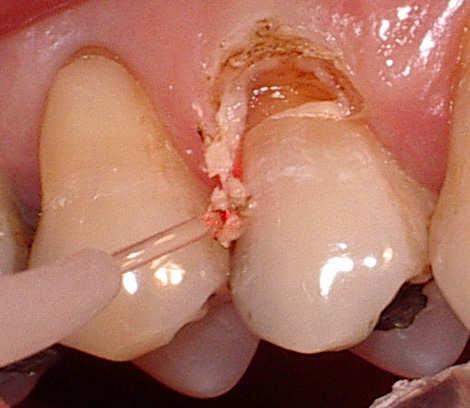

A palatal view of a maxillary premolar during a

crown lengthening procedure.

Crown lengthening is a surgical procedure performed by a dentist to expose a greater amount of tooth structure for the purpose of subsequently restoring the tooth prosthetically. This is done by incising the gingival tissue around a tooth and, after temporarily displacing the soft tissue, predictably removing a given height of alveolar bone from the circumference of the tooth or teeth being operated on. While many general dentists perform this procedure, they frequently refer such cases to periodontists.